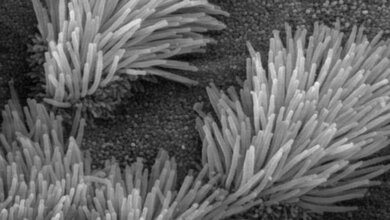

Jetzt hat das Team um Prof. Dr. Marcus Mall, damaliger und aktueller Studienleiter, erstmals untersucht, inwiefern diese Therapie auch langfristig, das heißt über mindestens zwölf Monate hinweg, hilft. Dafür haben die Forscherinnen und Forscher das Sputum, das Atemwegssekret, genauer betrachtet. „Bei Patientinnen/Patienten mit Mukoviszidose ist der Schleim in den Atemwegen sehr zäh, weil er zu wenig Wasser enthält und die schleimbildenden Moleküle, die sogenannten Muzine, zu stark chemisch miteinander verklebt sind. Der daraus resultierende zähe Schleim verstopft die Atemwege, erschwert damit die Atmung und führt bei den Betroffenen zu einer chronischen bakteriellen Infektion und Entzündung der Lunge“, erklärt Prof. Mall, Direktor der Klinik für Pädiatrie mit Schwerpunkt Pneumologie, Immunologie und Intensivmedizin und des Christiane Herzog Mukoviszidose-Zentrums der Charité.

Die Wissenschaftlerinnen und Wissenschaftler zeigen in der aktuellen Studie, dass die Dreifachtherapie mit Elexacaftor, Tezacaftor und Ivacaftor bei Patientinnen und Patienten mit Mukoviszidose dafür sorgt, dass das Atemwegssekret weniger zäh ist und die Entzündung und die bakterielle Infektion in der Lunge abnehmen. „Und das über die gesamte Dauer der Studie von einem Jahr. Das ist deshalb so bedeutsam, weil frühere Medikationen wieder zu einem Anstieg der Bakterienlast in den Atemwegen geführt hatten“, erläutert Dr. Simon Gräber, ebenfalls von der Klinik für Pädiatrie mit Schwerpunkt Pneumologie, Immunologie und Intensivmedizin der Charité und Co-Leiter der Studie. An dieser nahmen 79 Jugendliche und Erwachsene mit Mukoviszidose und einer chronischen Lungenerkrankung teil.

„Wir werden weiterhin intensiv daran forschen, wie Therapien, die Mukoviszidose über die krankheitsverursachenden molekularen Defekte angreifen – wie die jetzt untersuchte Dreifachmedikation – noch effektiver werden können. Hierzu gehört insbesondere ein früher Therapiebeginn im Kleinkindalter mit dem Ziel, chronische Lungenveränderungen möglichst zu verhindern“, berichtet Prof. Mall. „Außerdem steht diese Therapie für rund zehn Prozent unserer Patientinnen/Patienten aufgrund ihrer genetischen Voraussetzungen aktuell nicht zur Verfügung“, ergänzt Dr. Gräber. „Daher forschen wir auch mit Hochdruck an neuen molekularen Therapieansätzen, um alle Menschen mit Mukoviszidose effektiv behandeln zu können.“ Zudem arbeiten die Wissenschaftlerinnen und Wissenschaftler daran, die Fehlfunktion des Schleims bei Mukoviszidose besser zu verstehen und neue schleimlösende Wirkstoffe zu entwickeln. Davon sollen dann ebenfalls Patientinnen und Patienten mit häufigen chronisch-entzündlichen Lungenerkrankungen wie Asthma oder COPD profitieren.